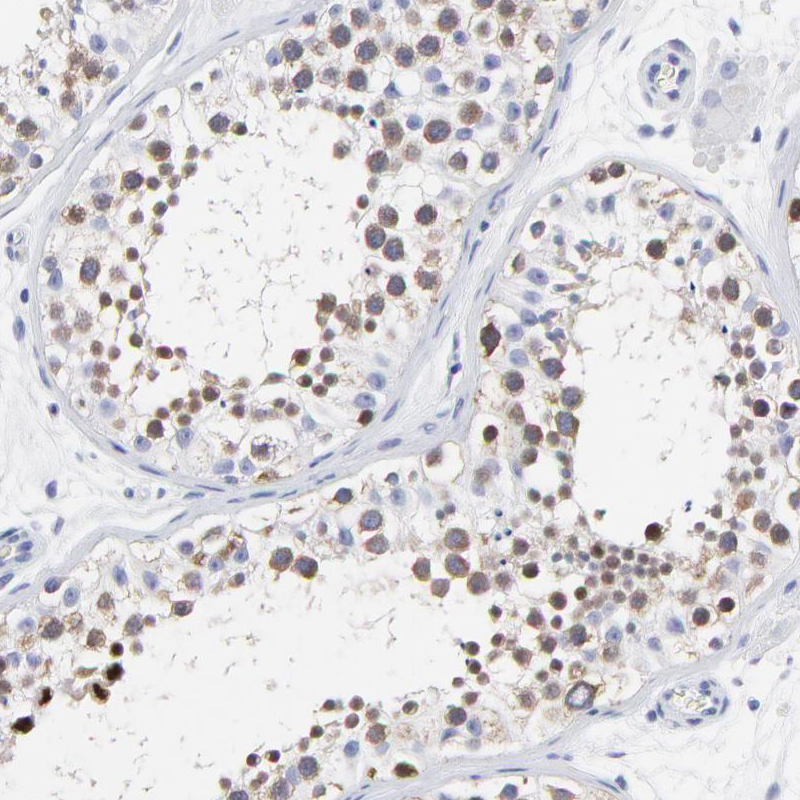

Immunohistochemistry analysis in human testis and kidney tissues using HPA003008 antibody. Corresponding NCAPH RNA-seq data are presented for the same tissues.